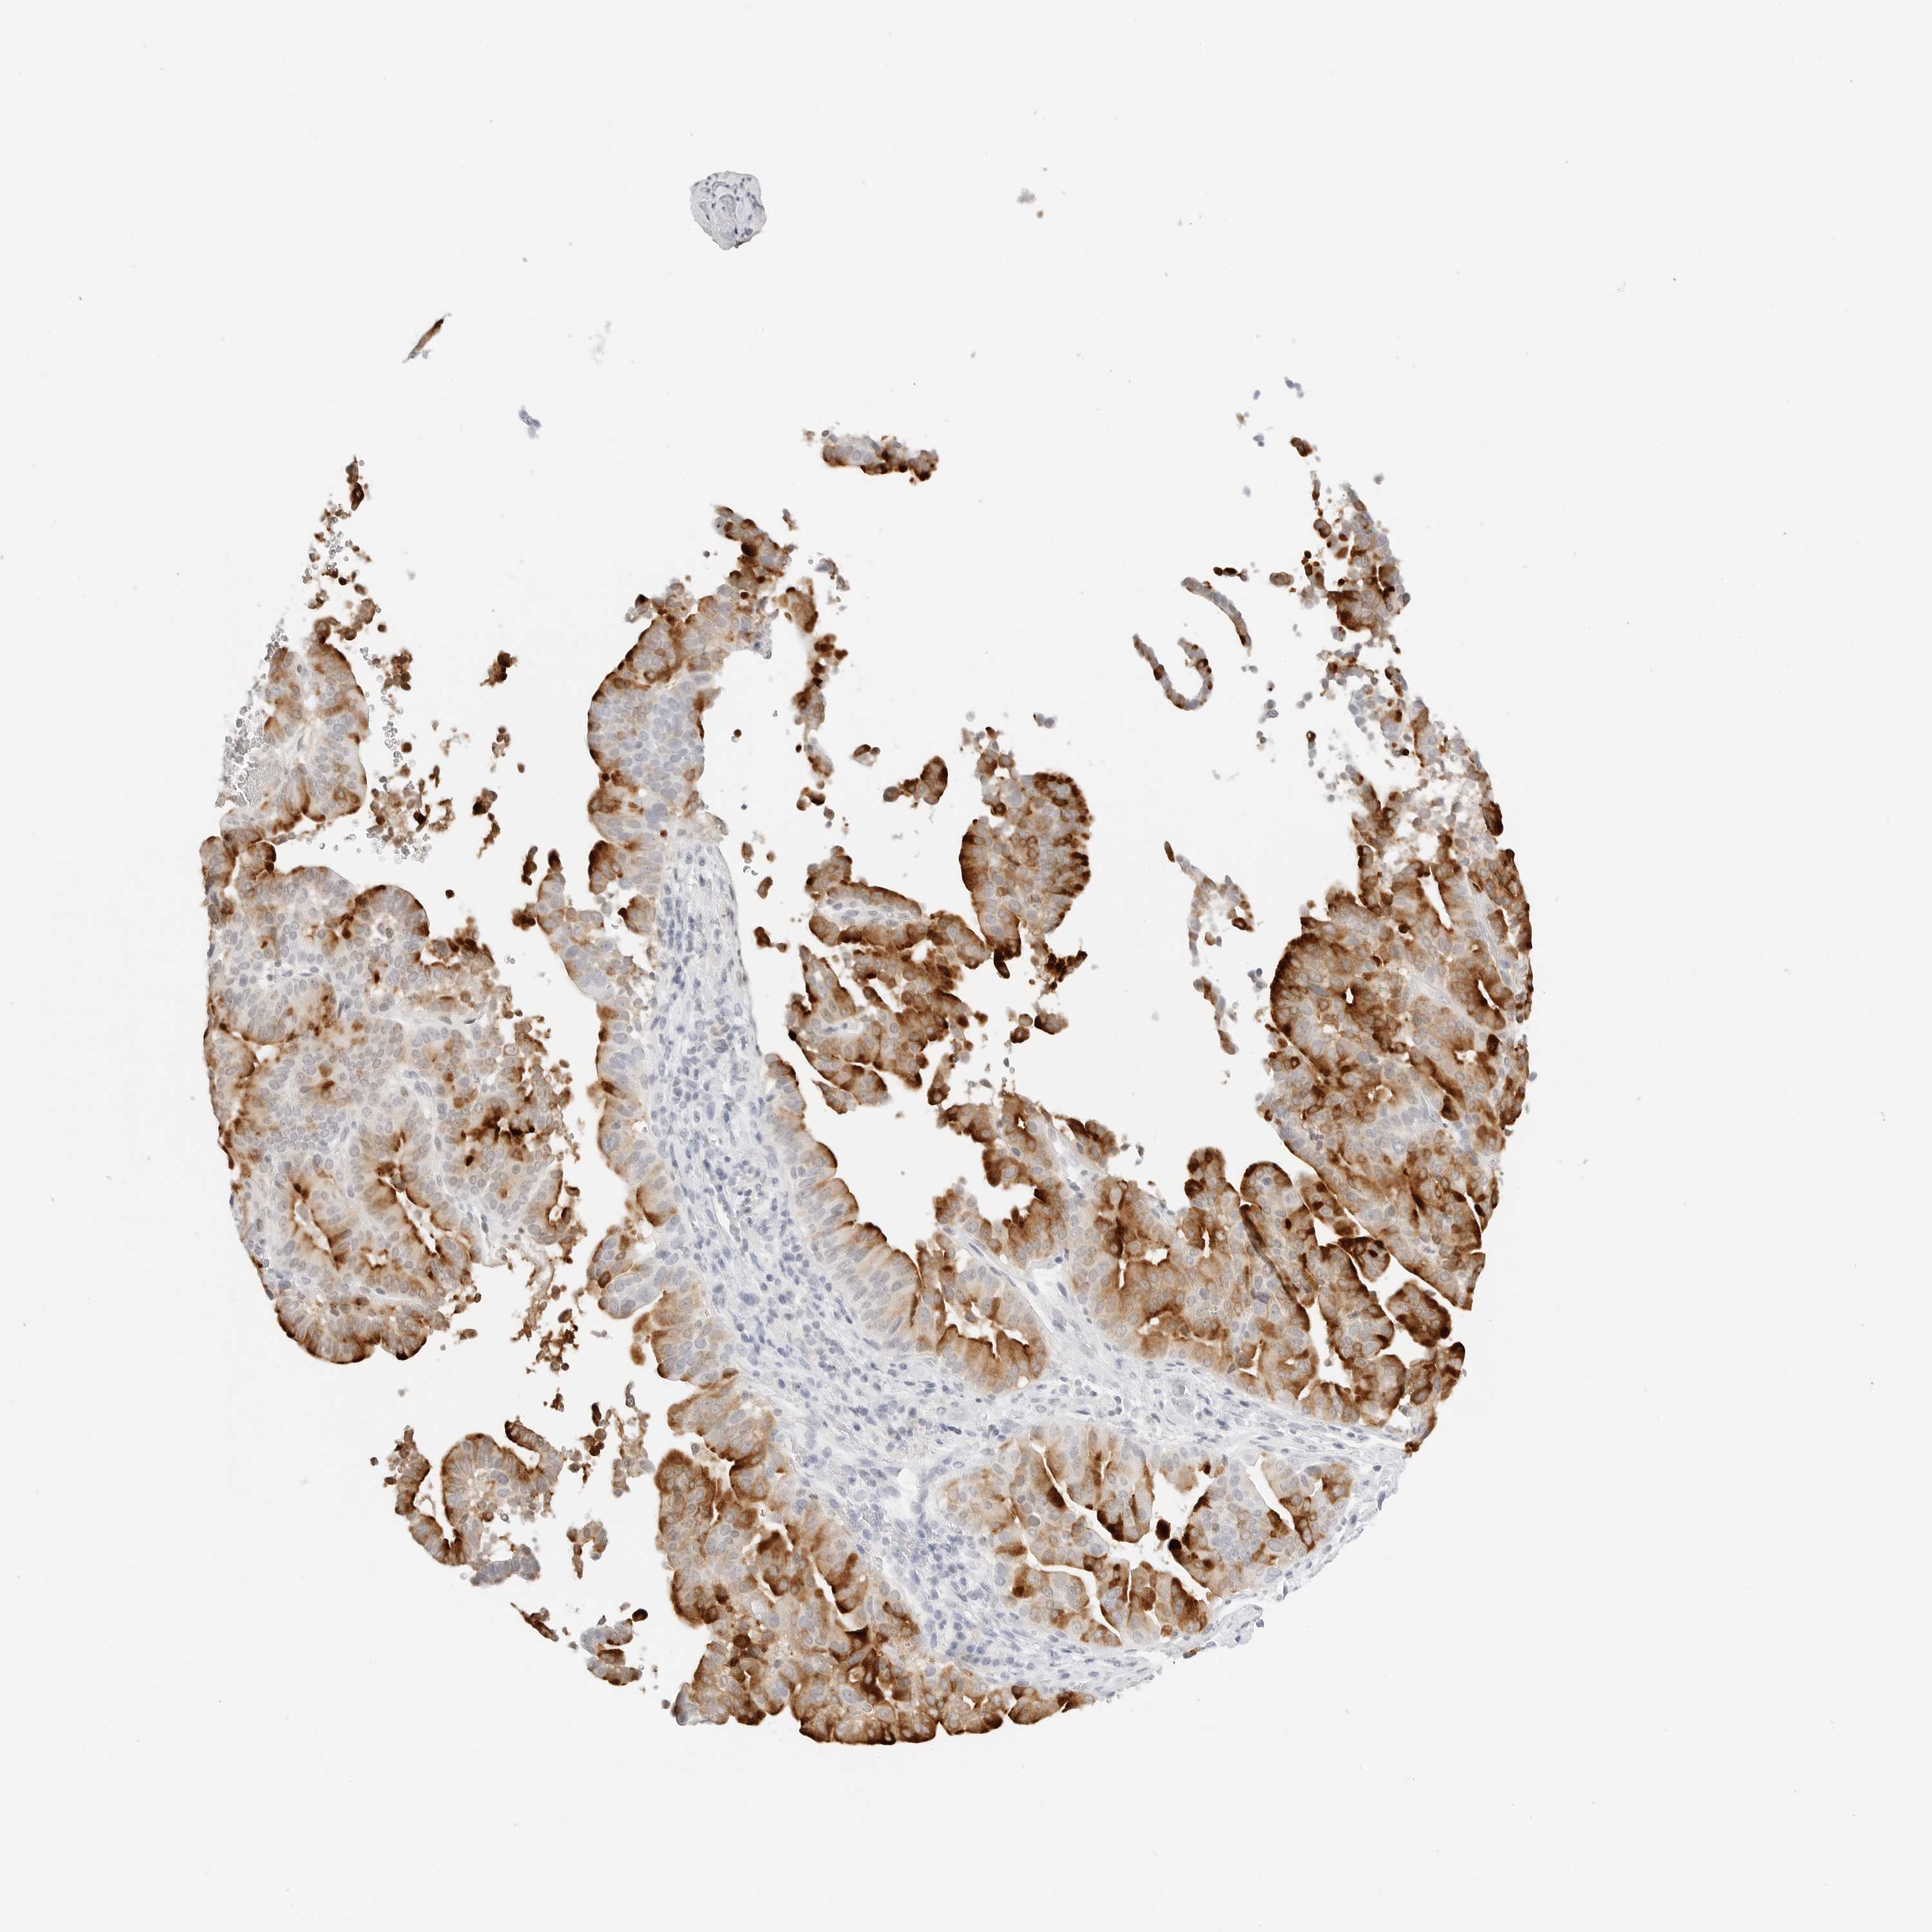

LIVER CANCER - Protein expressioni

A mouse-over function shows sample information and annotation data. Click on an image to view it in a full screen mode. Samples can be filtered based on level of antibody staining by selecting one or several of the following categories: high, medium, low and not detected. The assay and annotation is described here.

Note that samples used for immunohistochemistry by the Human Protein Atlas do not correspond to samples in the TCGA dataset.

Antibody stainingi

Antibody staining in the annotated cell types in the current human tissue is reported as not detected, low, medium, or high, based on conventional immunohistochemistry profiling in selected tissues. This score is based on the combination of the staining intensity and fraction of stained cells.

Each image is clickable and will lead to virtual microscopy that enables deeper exploration of all samples and also displays staining intensity scores, fraction scores and subcellular localization as well as patient and tissue information for each sample.

Antibody HPA036705

Antibody CAB025834

Staining

High

Medium

Low

Not detected

Intensity

Strong

Moderate

Weak

Negative

Quantity

>75%

75%-25%

<25%

None

Location

Nuclear

Cytoplasmic/membranous

Cytoplasmic/membranous,nuclear

Cholangiocarcinoma

Carcinoma, Hepatocellular, NOS